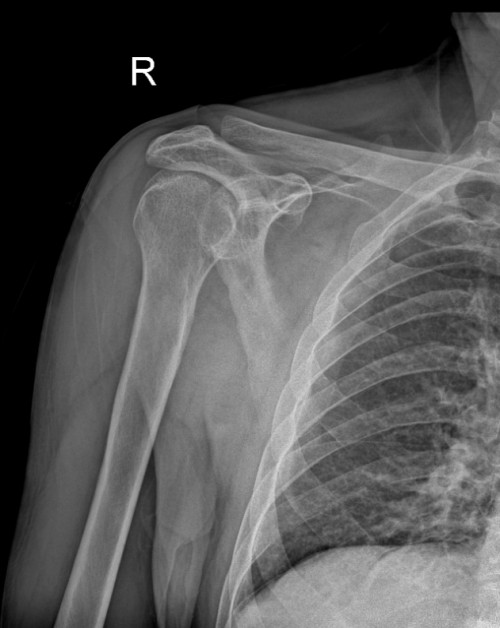

另一名为71岁患者张某,因车祸致右侧肩关节疼痛、活动受限,由120紧急送医。经检查确诊为右肩关节前脱位,排除骨折后,国华与李泰锋立即为其进行手法复位。复位后患者疼痛显著缓解,肩关节活动功能即刻恢复正常。家属激动表示:“老人年纪大了,我们原本非常担心需要开刀手术,没想到手法复位就解决了问题!”

复位后